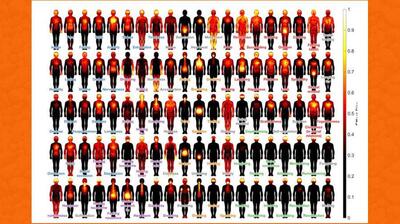

فیزیوتراپی زانو با لیزر پرتوان یکی از روش های موثر در درمان زانودرد و عامل بوجود آورنده آن است. درمان با لیزر پرتوان سبب افزایش میزان انرژی در دسترس سلول ها برای ترمیم ، بازسازی و فعالیت های حیاتی می شود و از این طریق روند بهبودی را سرعت می بخشد.

بررسی شواهد اخیر این سوال را مطرح میکند که ورزش چقدر میتواند برای کاهش درد آرتریت زانو مفید باشد.

درد زانو بسیار شایعتر از آن است که تصور میشود. متخصصان معتقدند ورزش، بهویژه پیلاتس، به سلامت زانوها کمک میکند.

حدود ۲۵ درصد بزرگسالان به زانودرد دچارند.